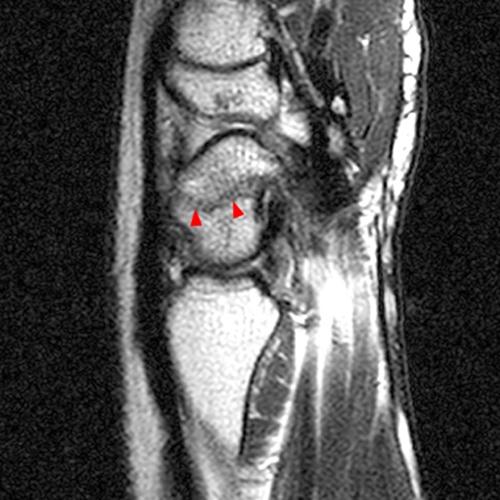

Figure 2: The axial T1-weighted (2A), axial fat-suppressed proton density-weighted (2B), and coronal fat-suppressed proton density-weighted (2C) images demonstrate a thickened extensor retinaculum, surrounding soft tissue edema, and fluid signal in the first extensor compartment of the wrist (arrowheads). Marrow edema is noted within the subjacent radius (asterisks). A single extensor pollicis brevis and two abductor pollicis longus tendon slips are present with heterogeneous intrinsic signal.

De Quervain’s Tenosynovitis.